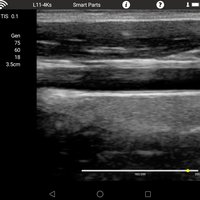

Linearsonde (L11-4Ks) 7,5 MHz 6-11 MHz L40 Gefäße, Small Parts, Anästhesie, Orthopädie